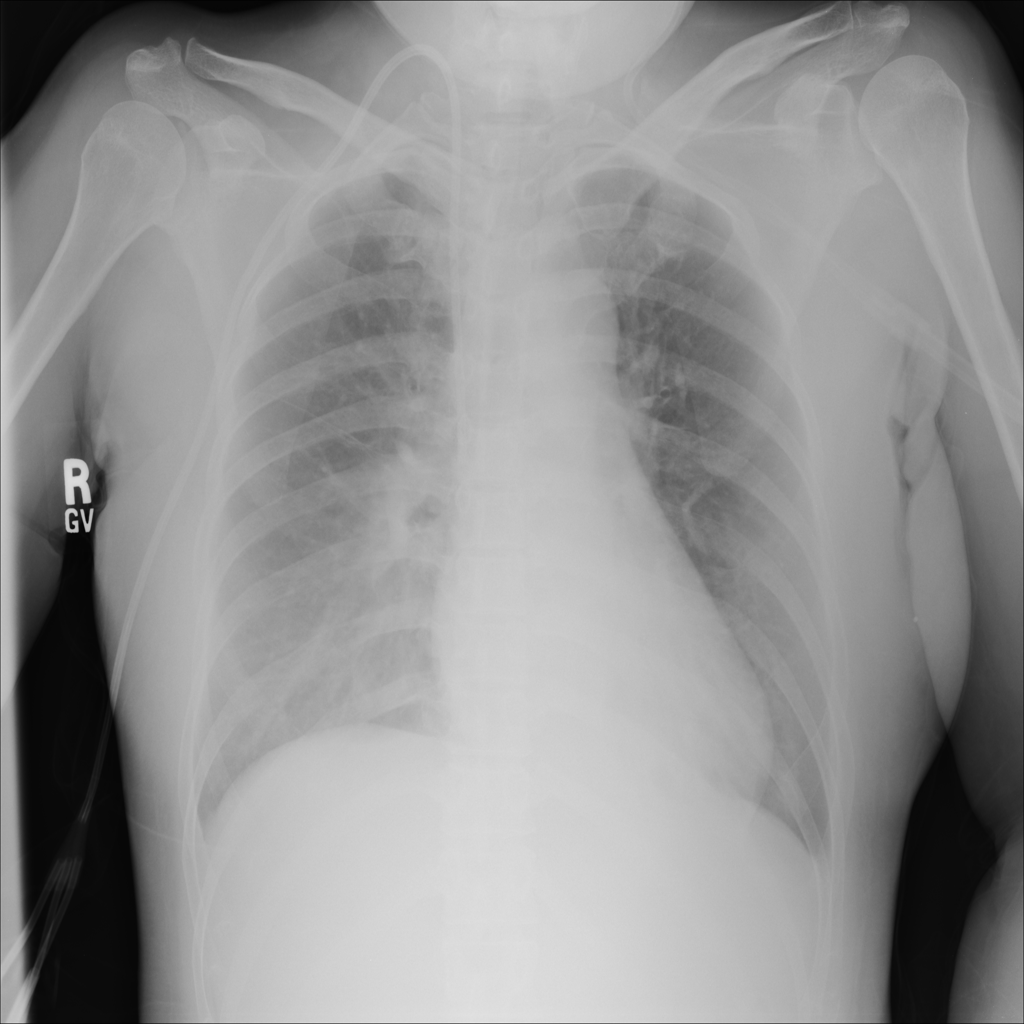

PAT-E828 · IMG-004Edema

PAT-E828 · IMG-004

AP